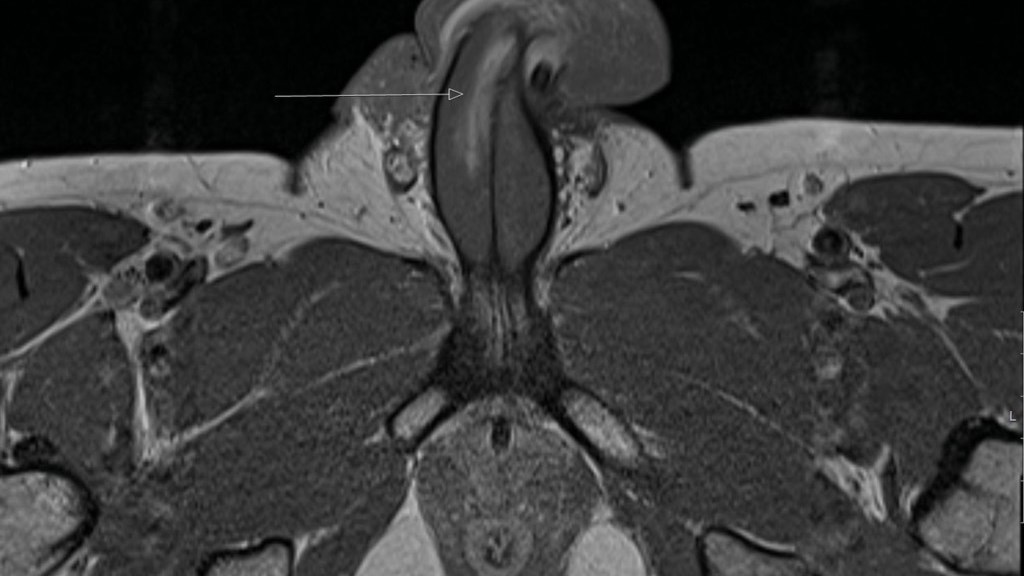

Είπαν ότι όλα τα κατάγματα του πέους που είχαν καταγραφεί στο παρελθόν ήταν οριζόντια. Αλλά σε αυτή την περίπτωση χωρίζει το tunica albuginea – το προστατευτικό στρώμα γύρω από τον στυτικό ιστό που αντλεί αίμα σε αυτήν την περιοχή. Ο γιατρός είπε ότι δεν ακούστηκε ήχος «αναδυόμενου» όταν συνέβη το σπάσιμο, το οποίο συμβαίνει όταν τα κατάγματα είναι οριζόντια. Τα σηραγγώδη σώματα συγκρατούνται από μια ισχυρή μεμβράνη που ονομάζεται ινώδης χιτώνας. Όταν ένας άνδρας υποφέρει από κάταγμα πέους, ουσιαστικά έχει σπάσει αυτή η ισχυρή μεμβράνη.